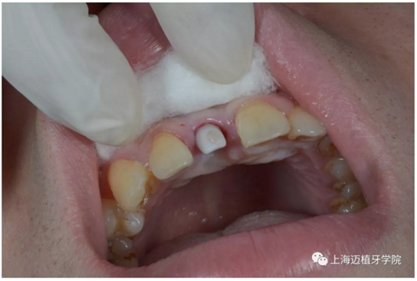

3月后恢復(fù)良好,上愈合基臺(tái)

2周后袖口成形